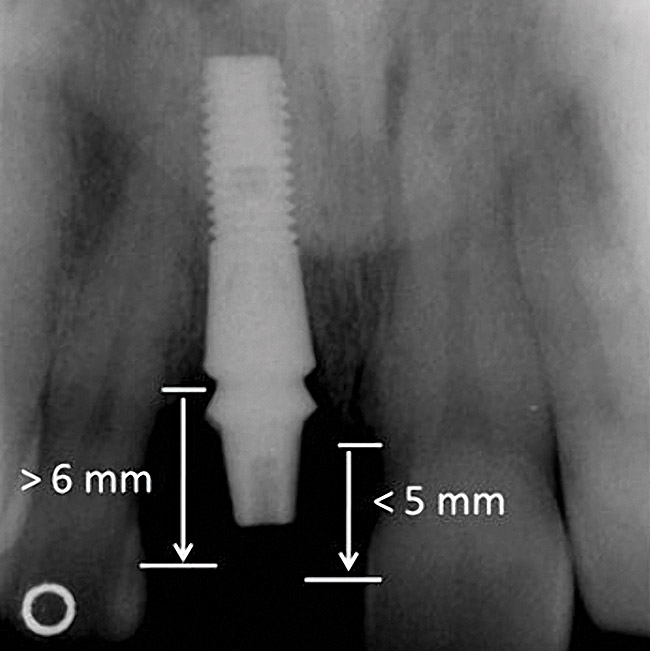

Figure 5  Characterization of the interproximal bone and tooth contacts: A periapical radiograph assists in measuring the distance from bone crest to the adjacent tooth contact points for missing tooth No. 8. The mesial bone crest to the adjacent tooth contact distance is < 5 mm, while the distal bone crest to adjacent tooth contact distance is > 6 mm (Fig 4). One-year following implant placement, conservation of these dimensions is revealed (Fig 5). The clinical photograph (Fig 6) of the lateral incisor adjacent to tooth No. 8 implant crown demonstrates that the absence of distal interproximal (papilla) fill related to the observed bone crest to contact distance exceeds 6 mm.

Figure 5

Figure 6  Characterization of the interproximal bone and tooth contacts: A periapical radiograph assists in measuring the distance from bone crest to the adjacent tooth contact points for missing tooth No. 8. The mesial bone crest to the adjacent tooth contact distance is < 5 mm, while the distal bone crest to adjacent tooth contact distance is > 6 mm (Fig 4). One-year following implant placement, conservation of these dimensions is revealed (Fig 5). The clinical photograph (Fig 6) of the lateral incisor adjacent to tooth No. 8 implant crown demonstrates that the absence of distal interproximal (papilla) fill related to the observed bone crest to contact distance exceeds 6 mm.

Figure 6